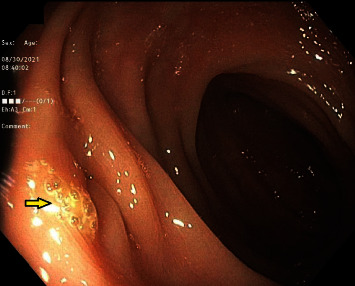

Colovesical fistula is an infrequent complication of diverticular disease that presents with pneumaturia, fecaluria, dysuria and, rarely, hematuria or hematochezia. Here we present a case of concurrent hematuria and rectal bleeding arising from a diverticular bleed traversing a previously undiagnosed colovesical fistula. Other causes of colovesical fistula include Crohn's disease, radiation, and malignancy, though it is most commonly caused by complicated diverticulitis as in this case. Computed tomography (CT) imaging, cystoscopy, and gastrograffin enema have been described as high-yield diagnostic tests. Interestingly, colonoscopy is only successful in diagnosing colovesical fistula in approximately 55% of cases. Management often requires surgical intervention, as in this case, given limited success with conservative management. Colovesical fistula should be considered in patients presenting with fecaluria, pneumaturia, and dysuria as well as in cases of hematuria.